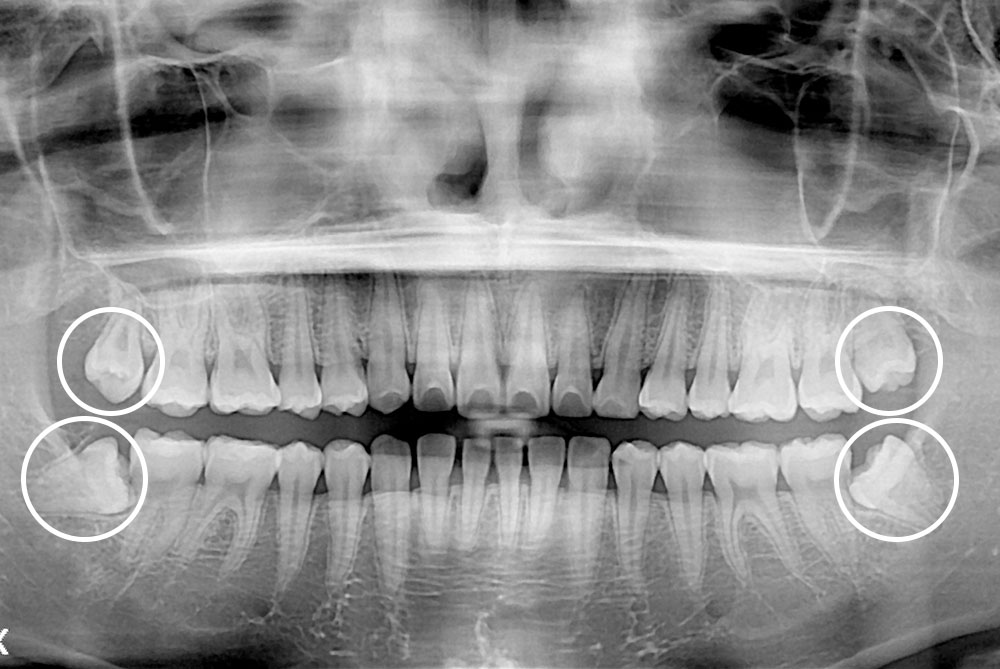

[사랑니] 매복 사랑니 발치

치료전 : 2019-08-23